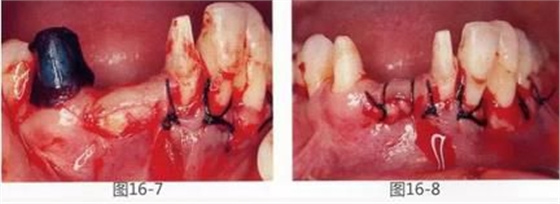

圖16-7 采集得到的結(jié)締組織瓣。

圖16-8 將上皮部分切離時。